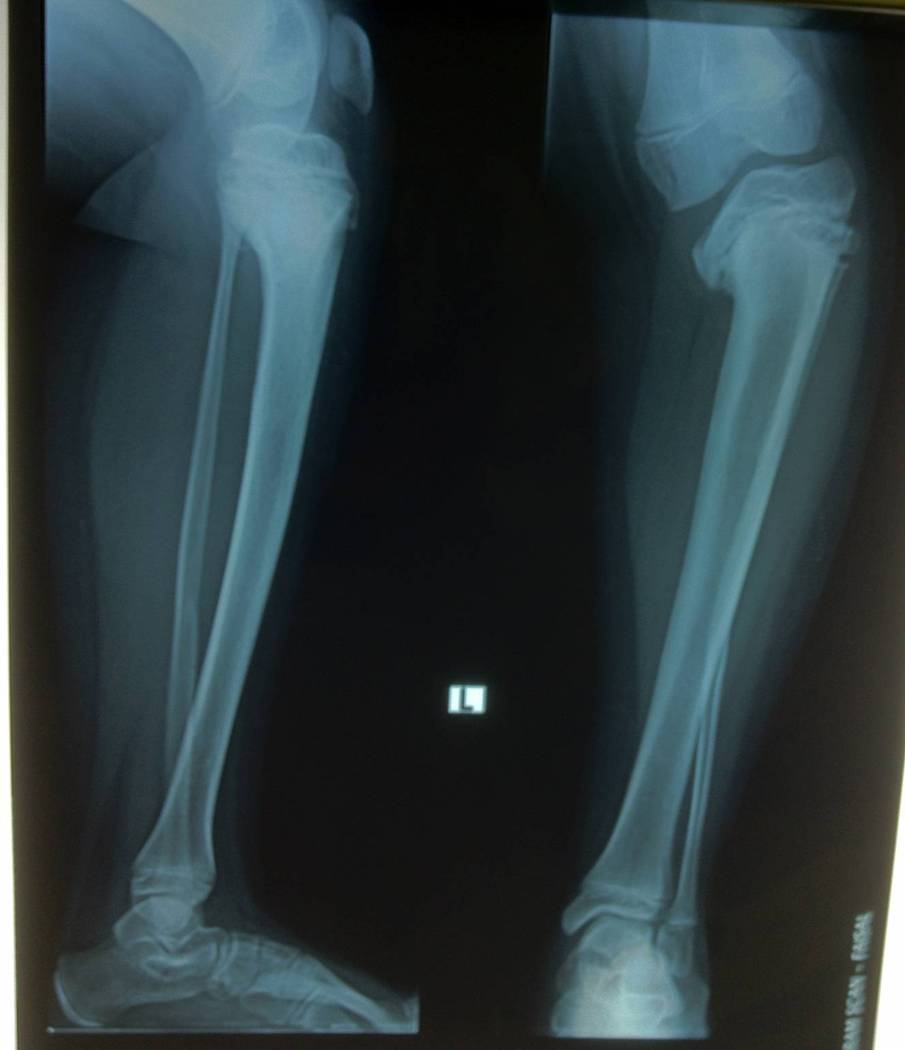

Blount disease is a developmental disorder characterized by disordered growth of the medial aspect of the proximal tibial physis resulting in progressive lower limb deformity. The deformity consists of varus, procurvatum, and internal rotation of the tibia, However, in the advanced stage of the disease, there is a bony bridge formation with medial plateau depression, joint instability, and leg length inequality, all of which have to be addressed by the proposed treatment. We treat this case by intra atticular osteotomy to elevation of medial plateau and another metaphyseal osteotomy to correct the varus and internal rotation deformities.

داء بلونت يطلق علي اعوجاج الساق المكون من هبوط باعلي الجزء الداخلي من اعلي عظمه الساق مع اعوجاج انسي بالساق و يتم علاج تلك الحالات بواسطه شقين عظميين احدهما خلال غظروف اعلي عظمه الساق والاخر بالجزء العلوي للساق مع الاستعدال التدريجي بواسطه مثبت خارجي مع العلم ان العلاج لا يرتبط بوزن المريض حيث يتم عمل العمليات بنجاح في الحالات السمنة الشديدة كما هو موضح بالصور